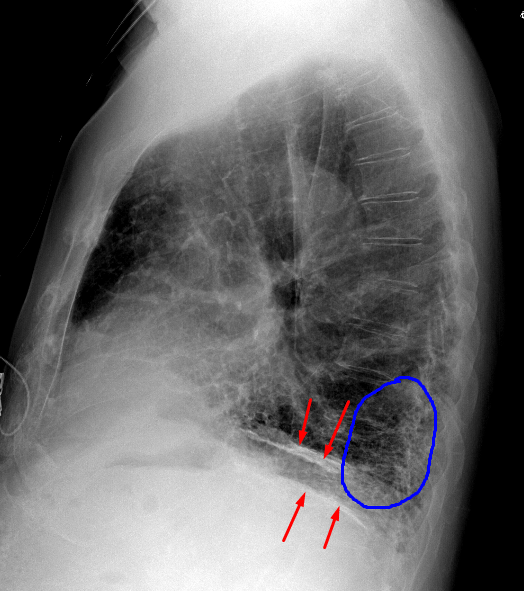

Age: 83

Sex: Male

Indication: Pre-op

Sample ReportBilateral pleural plaques and interstitial coarsening, most prominent at the lung bases. Findings are most suggestive of asbestosis. Consider chest CT for further evaluation.

No definite superimposed focal airspace disease.

Mild cardiomegaly.